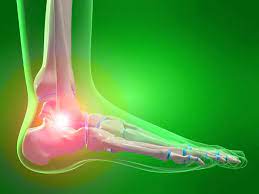

통풍은 높은 요산 농도로 인해 결정이 관절 주변에 쌓이면서 발생하는 만성적인 대사성 질환입니다. 이로 인해 관절과 주변 조직에 염증이 발생하며 통증, 부어오름, 열감 등의 증상이 나타날 수 있습니다. 주로 발 발가락의 관절에서 발생하지만 손, 발목, 무릎 등 다양한 관절에 영향을 미칠 수 있습니다. 통풍은 요산 결정이 관절 주변의 소프트 터치에 의해 활성화되거나 특정 상황에서 급작스럽게 악화될 수 있는 특징이 있습니다. 심각한 경우에는 관절 손상을 초래하여 일상생활에 큰 불편을 초래할 수 있습니다. 요산 결정의 쌓임을 예방하고 염증을 관리하는 것이 통풍 관리의 핵심입니다.

통풍의 증상

통풍은 주로 급격한 발작적인 증상을 보이며, 이는 주로 관절 부위에서 발생합니다. 통풍 발작의 주요 증상은 다음과 같습니다:

- 극심한 통증: 통풍 발작은 강한 통증을 동반합니다. 통증은 일반적으로 밤이나 새벽에 시작하여 관절 부위에 급격히 나타나며, 뚜렷한 통증을 유발합니다. 종종 "화살통 통증"이라고도 불리며, 통증의 강도는 매우 높을 수 있습니다.

- 부어오름과 발적: 통풍 발작 부위의 관절은 붓고 붉게 변할 수 있습니다. 특히 발가락의 발적이 흔하며, 관절 주위에 염증이 발생하는 결과입니다.

- 열감과 민감도: 통풍 발작으로 인해 발작 부위는 뜨거워지고 민감해질 수 있습니다. 심한 경우, 신체의 발열과 함께 민감도가 증가하는 것을 경험할 수 있습니다.